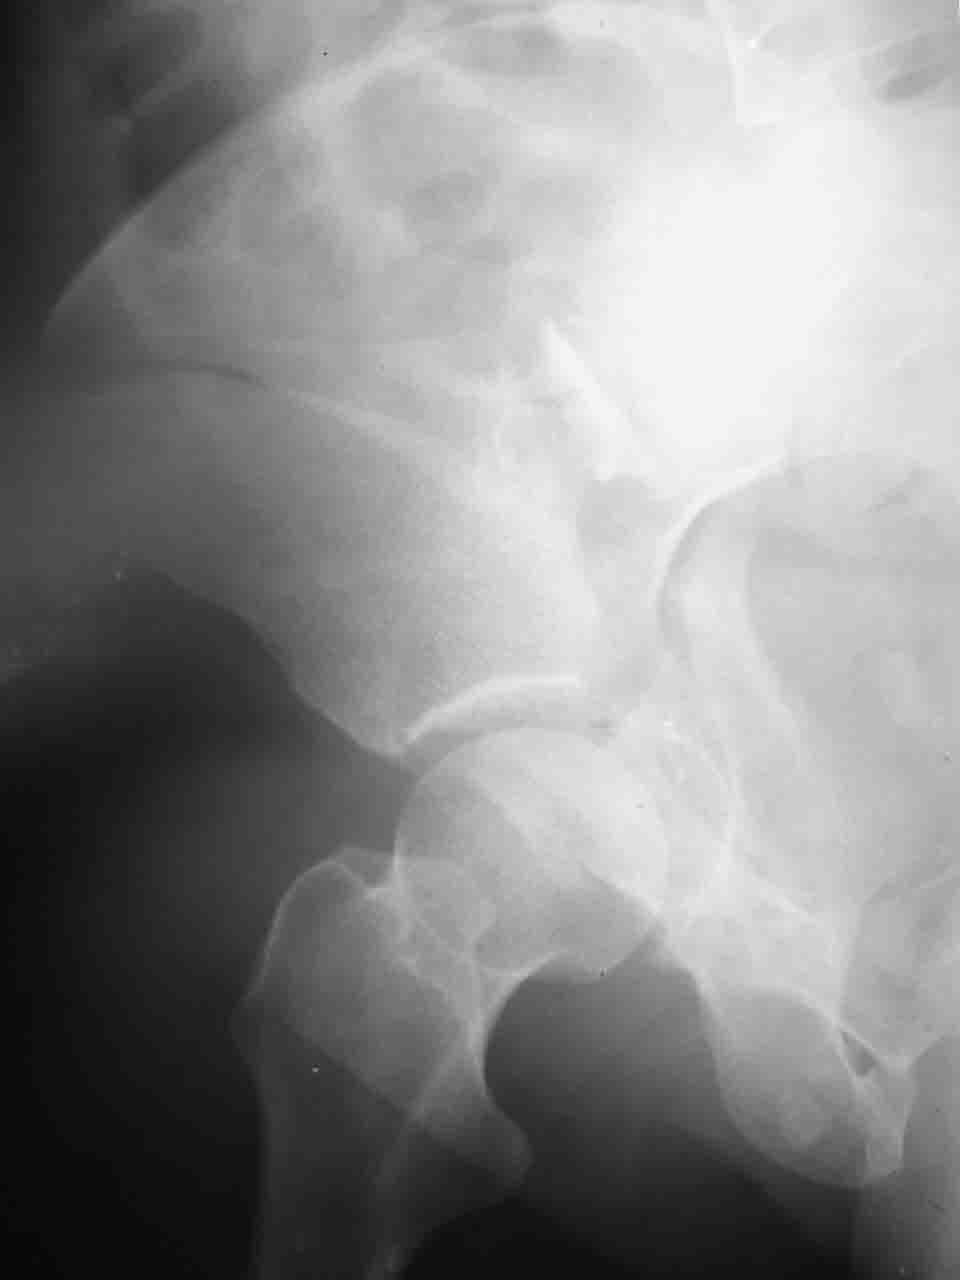

Вопрос доступа к вертлужной впадине при остеосинтезе задача не простая. Конечно, у Летурнеля и Тайла всё давно описано, нам остается только брать на вооружение. Но сами понимаете, что не бывает двух одинаковых ситуаций, поэтому в каждом случае вопрос решается сугубо индивидуально. Наша главная цель - восстановить анатомию с нанесением минимальной дополнительной травмы тазобедреннному суставу, думаю с этим никто не поспорит. Расширенный илиофеморальный доступ уж слишком травматичен (как сказал один коллега "таз лежит отдельно, больной отдельно").Стоит ли делать из пациента анатомический препарат для того чтобы легче ориентироваться. Да и нужно ли собирать всю "мозаику"? Мы применяли при таких операциях своеобразную операционную хитрость - сначала устраняли грубое смещение крыла под гребнем с фиксацией так называемой "плавающей" пластиной (временно фиксированной на двух винтах)- доступ или продлевали боковой, или делали небольшой дополнительный разрез над гребнем. Это позволяло устранить грубое смещение и захождение отломков тела повздошной кости, что значительно облегчало репозицию и остеосинтез впадины над сводом. Основное внимание конечно же уделяли нагружаемому задне-верхнему отделу. Сообщите ваш адрес, пришлю схемы и рентгенограммы.